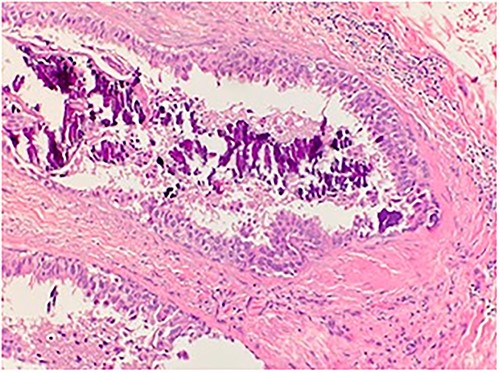

An 84-year-old female presented to the breast surgery office for biopsy proven malignant 2-cm palpable mass on physical examination in the right retroareolar region. Her medical history was significant for hypertension, diabetes mellitus, and stroke. She had a diagnostic bilateral mammogram and sonogram along with a biopsy of the site in question, at another outside facility, which had yielded invasive ductal carcinoma with perineural invasion. In addition, indeterminate linear microcalcifications were visualized in the central right breast 3-cm posterior to the mass and also in the central far posterior lower right breast. These warranted another diagnostic mammogram and sonogram. Repeat diagnostic mammogram and sonogram were remarkable for: biopsy-proven malignant 1.2-cm mass in the right retroareolar region. Additional suspicious microcalcifications 3- and 7-cm posterior to the mass were noted, classified as BIRADS 4. She underwent a stereotactic biopsy. Pathology for the retroareolar mass was positive for moderately differentiated invasive ductal carcinoma with perineural invasion and pathology for calcifications was positive for Ductal Carcinoma in Situ (Fig. 1). Invasive ductal carcinoma was positive for ER (95%), PR (50%), and negative for Her-2/Neu. Ductal Carcinoma In Situ was positive for ER (90%–95%) and negative for PR (0%). Subsequently, upon an extensive discussion with the various options including but not limited to lumpectomy and mastectomy, she elected to undergo a right simple mastectomy without reconstruction with right axillary sentinel node biopsy. Surgical pathology was remarkable for no evidence of active malignancy in any of the previously biopsied areas; evidence of nodular necrosis of tumor cells noted (Fig. 2) consistent with inflammatory reaction and fibrocystic changes. Patient was started on Anastrozole and the following postoperative course was unremarkable.

Microscopic examination shows high grade ductal carcinoma cells confined within the base membrane with necrosis. H&E 20×.